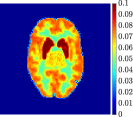

Figure 4, Figure 5, and Figure 6 show the mean images computed over the ten reconstructions obtained by the methods reg-AS-TR, reg-GN, and by the Matlab routine lsqcurvefit implementing a standard Trust-Region-Reflective least-squares algorithm [11, 10]. We used the noise-free IF and the perturbed IF with and of noise, respectively. Figure 7 contains mean and standard deviation values of the kinetic parameters computed over the ten reconstructions and over each one of the four homogeneous regions, for each one of the three noise levels on the IF.

In general, reg-AS-TR and lsqcurvefit seem to provide similar mean reconstructions, although uncertainties associated to lsqcurvefit are significantly bigger. On the other hand reg-GN seems to systematically underestimate the parameter values within region . Furthermore and as expected, for all methods the quality of the parametric reconstructions deteriorates with increasing noise levels; this is more clear from the and parametric images, probably due to the different sensitivities of the data with respect to the model parameters [37]. In reg-GN and lsqcurvefit some artifacts can be observed at the edges of the homogeneous regions, especially around region and region , whereas the effect of regularization in reg-AS-TR results in a reduced presence of artifacts while the structure of the regions is preserved. This general trend is confirmed by the error-bar plots of Figure 7. Finally, the frames in Figure 8 corresponding to reg-AS-TR show a significant improvement of the image quality with respect to what is provided by the other two approaches.